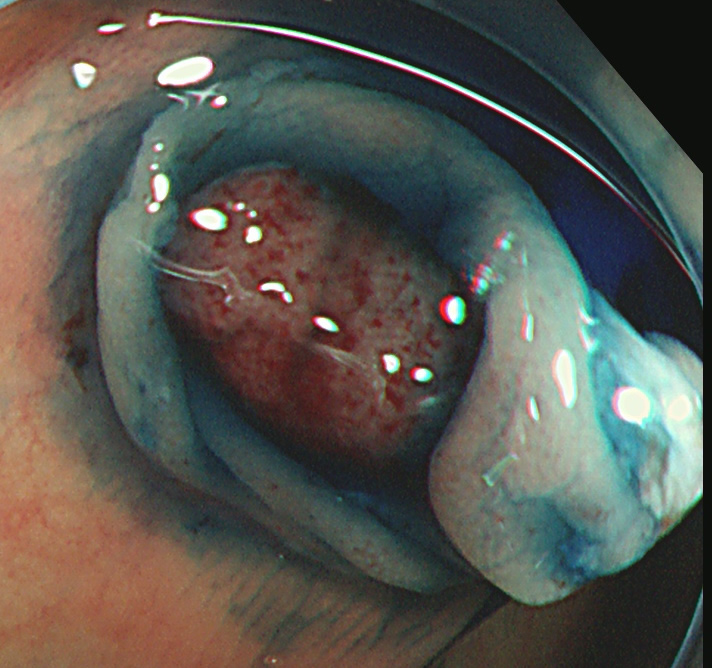

Extended Cold法法で切除された検体は「目玉焼き」のようになります。「黄身」が病変で、「白み」が周囲の正常組織(余白、マージン)です。

腫瘍の取り残しを防ぐために「白み(余白)の大きな目玉焼き」にすることが、最大のポイントです。